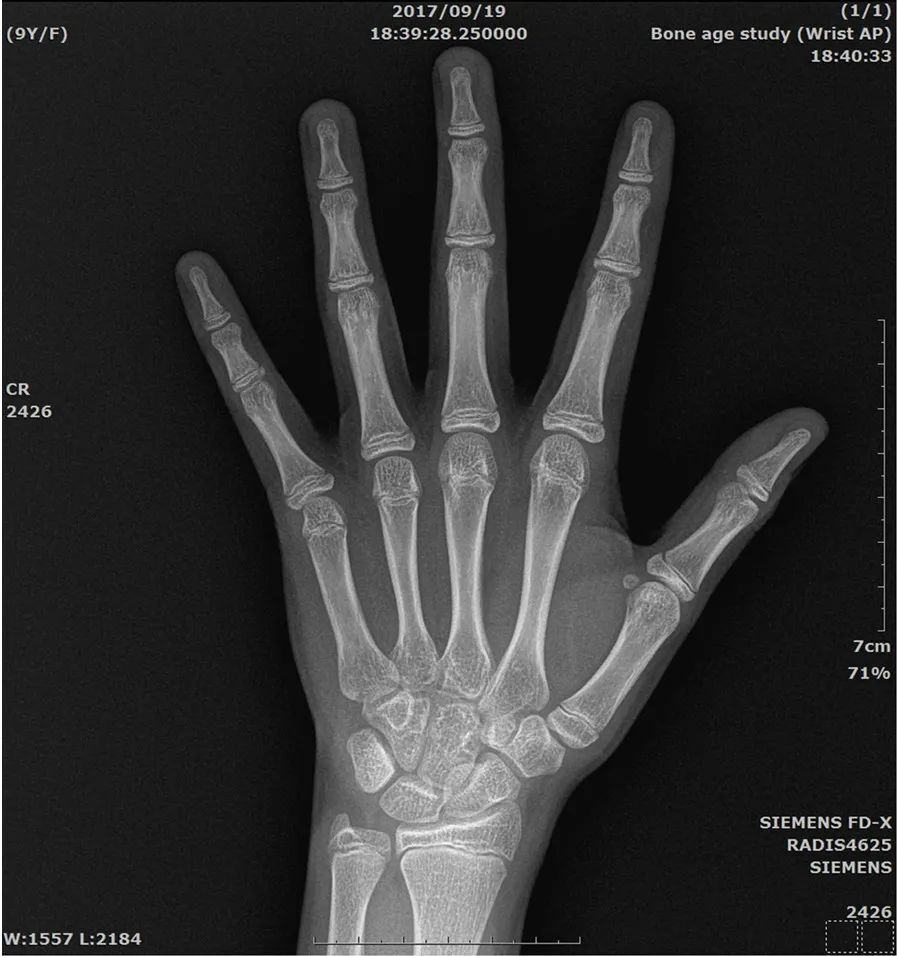

目前最被普遍使用的方法是左手 X 光照射的骨龄评估,以手掌 X 光片评估骨龄的方法有几个好处,因为手掌骨节多,相对的骨化中心也多,较容易比较出不同阶段的骨骼发育。

之所以选择左手,是因为惯用右手的人多,相对地右手也较容易受伤,因此评估左手比右手来的稳定可靠。另外,左手 X 光照射远离身体重要器官,其辐射剂量对身体器官影响极小。

左手 X 光照射的骨龄评估,很重要的是 X 光片的正确拍摄及清晰度,正确照法必须注意下列事项:

左手面向下,平放在片夹上,指头外展,由手背向手掌方向照射。

中指方向应保持与前臂之方向相同,成一直线。

手指自然平放,不必紧压片夹,拇指自然外展约 30 度角。

X 光照射管中心点,应对准中指第三指节之节结末端,约在手背正中心。

X 光照射管应垂直片夹照射,与片夹之距离 76 公分。

X 光之设定在 45~60 kVp,依年龄略调整。

X 光照射范围,包含桡骨与尺骨手腕侧 3~4 公分即足够,不必太多。

其方法是用左手张开由手背向手心正照之 X 光片和标准之骨龄图谱做比较。主要比对各骨逅出现之时间及生长盘和钙化骨头的形状变化,以最近似之标准骨龄图谱做出骨龄判读。